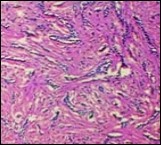

Lesions are generally superficial and infrequently invade lower dermis. Tendency for peri-neural or intra-neural infiltration, cogitated in adjunctive cutaneous carcinomas, is exceptional in desmoplastic trichoepithelioma. Nevertheless, desmoplastic trichoepithelioma can be exemplified as a component of particularly desmoplastic, cutaneous carcinomas demonstrating foci of peri-neural involvement 4, 5. Figure 1, Figure 2, Figure 3, Figure 4, Figure 5, Figure 6, Figure 7, Figure 8.

Figure 8.Desmoplastic fibrotic stroma demonstrating a thinned out, superimposed epithelium, fibrotic stroma and a dispersal of basaloid cell cords and aggregates 15.